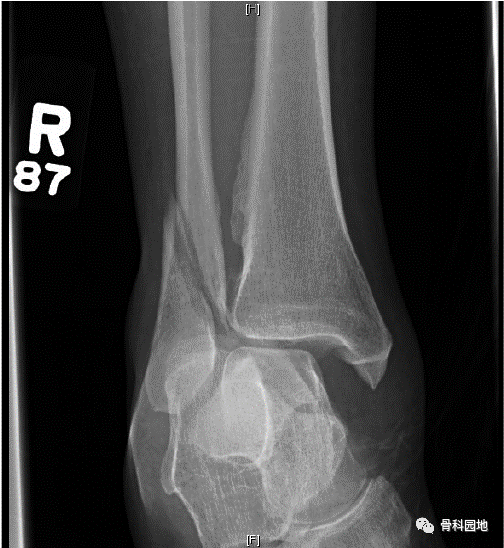

术后X线片: